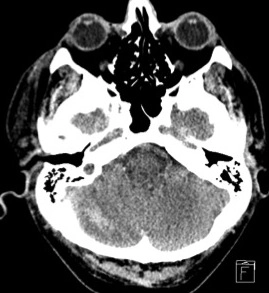

• Xuất huyết não do tăng huyết áp (Hypertensive Intracerebral Hemorrhage - HICH)